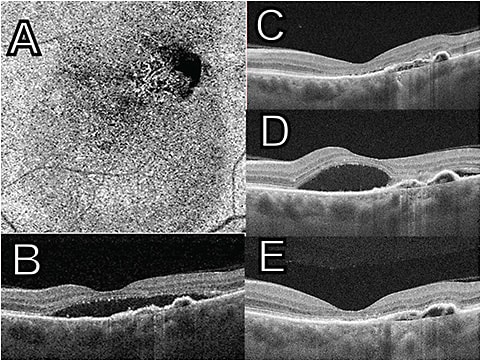

A recent study attempted to define the suitability of a step therapy approach with one of the most common and serious clinical scenarios in retina: the management of diabetic macular edema (DME). The report, from the DRCR Network (Protocol AC),4 compared outcomes for patients with center-involving DME at 2 years when starting off with intravitreal aflibercept vs starting with intravitreal bevacizumab.

Participants initially received injections of either aflibercept or bevacizumab every 4 weeks for 24 weeks. If eyes assigned bevacizumab failed to reach the preset benchmarks of vision and macular edema starting at 12 weeks, the eye was switched to aflibercept. Follow-up visits took place every 4 weeks during the first year, followed by every 4 weeks to 16 weeks during the second year, depending on the examination findings.

At 24 weeks and 52 weeks, switching criteria were met in 39% and 60%, respectively, in the bevacizumab-first group. At the end of 2 years, 70% of the bevacizumab group needed to be switched to aflibercept according to the preset criteria. After this time, eyes in both groups had similar visual acuity outcomes, improving on average approximately 3 lines on an eye chart, compared to the start of the trial. Eyes in the aflibercept monotherapy group required fewer injections: a mean of 14.6±4.1 injections vs those in the bevacizumab-first group, who required 16.1±4.1 injections.